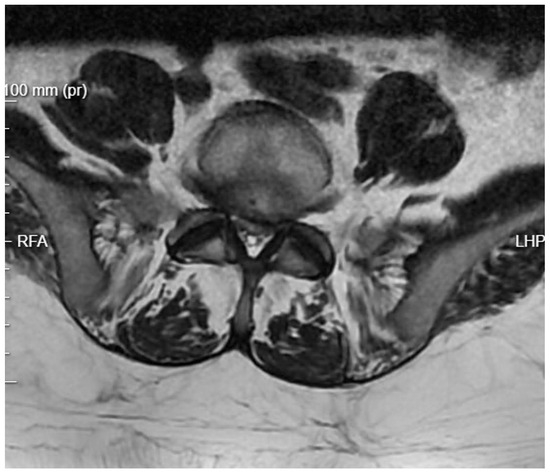

Long-term Outcome: Two months later, after stabilization of his renal condition, the patient underwent control diagnostics. MRI results were satisfactory, and clinically, the patient was able to move with the assistance of a walker (Figure 8). The pain was moderate and allowed for relatively normal functioning. The patient was referred to the rehabilitation department for further improvement.

Figure 8. T2 axial MRI image at the L4/L5 level following previous transforaminal endoscopic debridement.